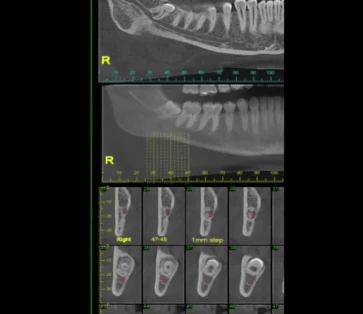

צילום שיני בינה

ישנם מגוון צילומי שיניים המשמשים לעזר בטיפולי שיניים, אולם לא כולם מתאימים להערכה של שיני בינה. צילומי נשך, צילום פנורמי ועוד. -